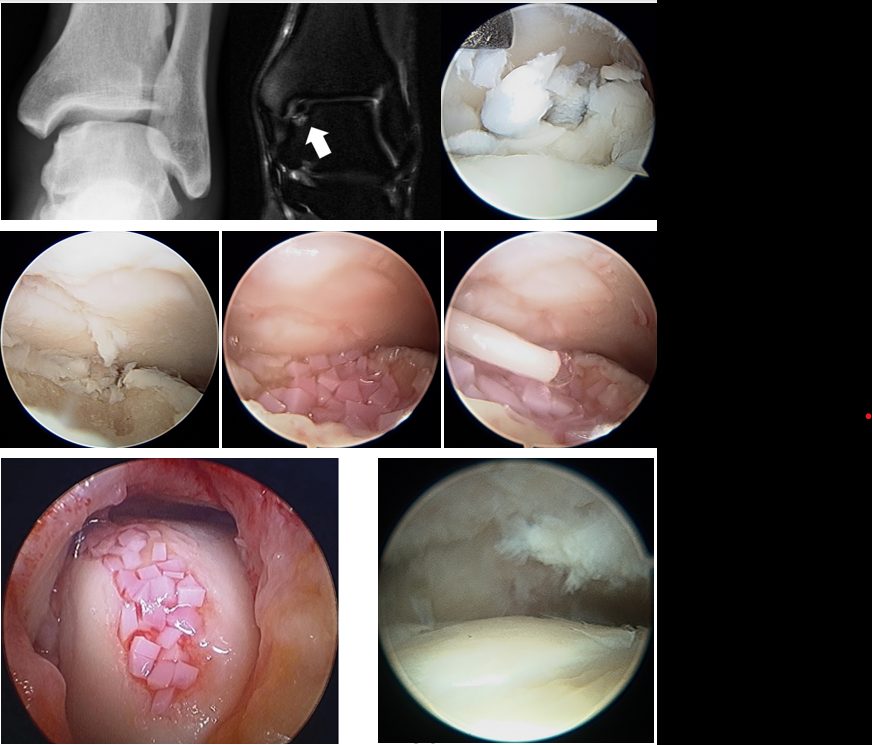

Рис. 9. Артроскопический вид различных стадий остеохондральных повреждений таранной кости

Костномозговая стимуляция (BMS / микрофрактуринг)

Принцип: перфорация субхондральной пластинки → выход мезенхимальных стволовых клеток и факторов роста из костного мозга → формирование кровяного сгустка в зоне дефекта → дифференцировка в фиброхрящ.

Техника (артроскопическая):

- Диагностическая артроскопия через стандартные порталы (передне-медиальный рабочий, передне-латеральный обзорный)

- Идентификация и оценка ОХП пробником

- Дебридмент: удаление нестабильного хряща малой кюреткой. Стабильные края хряща сохраняются и формируются вертикально (perpendicular) для удержания кровяного сгустка

- Удаление склеротической субхондральной пластинки кюреткой

- Микрофрактуринг: перфорация субхондральной кости шилом (awl, обычно 60-65°) перпендикулярно поверхности. Отверстия на расстоянии 3-4 мм друг от друга. Глубина — до появления жировых капель (fat droplets), что подтверждает проникновение в костный мозг

- Снижение давления ирригации → визуализация кровотечения из перфорационных отверстий (подтверждение эффективности)

- Формирование стабильного кровяного сгустка (super clot)

Показания: дефект < 1.0 см² (< 150 мм²) без значительного костного дефекта. При дефектах > 150 мм² (15 мм в диаметре) — значительно худшие результаты.

Рис. 10. Артроскопическое микрофрактурирование субхондральной пластинки

BMS + скаффолд (M-BMS / AMIC)

Дополнение микрофрактуринга биорезорбируемой коллагеновой мембраной для улучшения качества регенерата — аутологичный матрикс-индуцированный хондрогенез (AMIC — Autologous Matrix-Induced Chondrogenesis).

Принцип: мембрана выполняет роль каркаса (scaffold), удерживая кровяной сгусток и мезенхимальные стволовые клетки в зоне дефекта, создавая оптимальное микроокружение для хондрогенной дифференцировки.

Показания: дефект ≥ 1.0 см²

Техника:

- Артроскопический или открытый дебридмент + микрофрактуринг (как описано выше)

- Измерение дефекта

- Вырезание мембраны (Chondro-Gide® — наибольшая доказательная база) по размеру дефекта

- Фиксация мембраны: фибриновый клей (Tisseel®) или резорбируемые швы

- Мембрана укладывается пористым слоем к кости (для адгезии клеток), гладким — к полости сустава

Предпочтительный скаффолд: Chondro-Gide® — двухслойная коллагеновая мембрана I/III типа. [Grade B, Level III — DGOU 2024]

Рис. 11. Закрытие дефекта коллагеновой мембраной (AMIC)